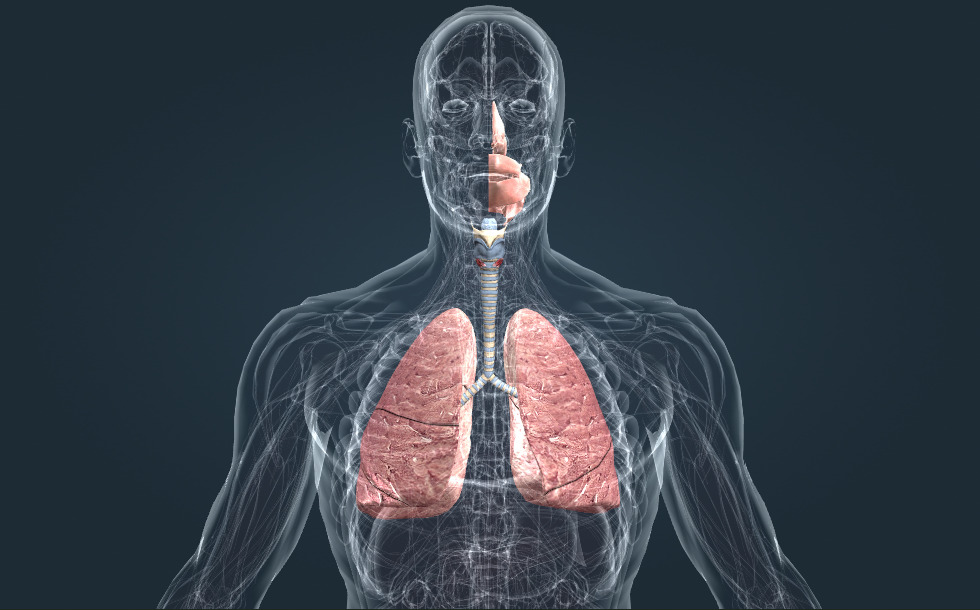

Hệ hô hấp

- khí quản

- thanh quản

- phổi

- khoang miệng

- khoang mũi

- hầu

- phế quản gốc

Các quá trình dị hóa trong cơ thể chúng ta cần sử dụng oxy và tạo ra carbon dioxit. Sự hấp thu oxy và giải phóng carbon dioxit đều diễn ra tại phổi. Ở trạng thái thư giãn, chúng ta hít vào khoảng 16 lần một phút và trao đổi khoảng nửa lít không khí mỗi lần. Ung thư phổi là một căn bệnh nghiêm trọng của phổi; hút thuốc lá làm người hút rất dễ mắc căn bệnh này.

Các quá trình dị hóa trong cơ thể chúng ta cần sử dụng oxy và tạo ra carbon dioxit. Sự hấp thu oxy và giải phóng carbon dioxit đều diễn ra tại phổi. Ở trạng thái thư giãn, chúng ta hít vào khoảng 16 lần một phút và trao đổi khoảng nửa lít không khí mỗi lần. Ung thư phổi là một căn bệnh nghiêm trọng của phổi; hút thuốc lá làm người hút rất dễ mắc căn bệnh này.